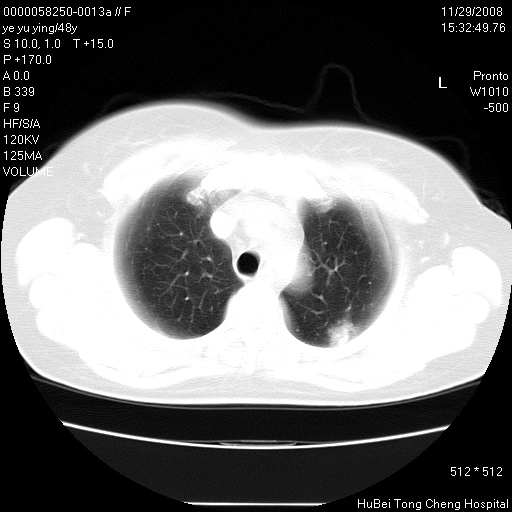

以下是引用huenhao在2008-11-29 22:11:00的发言:[br]脂肪肝,胆囊结石。左肺病灶建议定期复查。

以下是引用liuyue在2008-11-30 5:44:00的发言:[br]1.左肺病变,首先考虑感染性病变,转移待排;建议治疗后复查。[br]2.肝脏密度普遍减低,考虑与化疗有关。[br]3.胆囊结石.